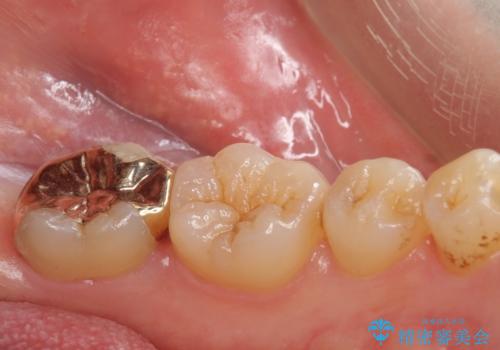

①ゴールドインレーによる治療

割れる心配がなく、歯質もセラミック治療よりも削らなくて済むが、審美的にセラミックより劣る。

二つの提案をしたところ、①を選択されたのでゴールドインレーによる治療を行いました。

- ゴールドインレー 11万円費用は治療当時の料金となります

ゴールドインレーは歯質との適合がよく

虫歯の再発リスクや割れるというリスクが低いです。